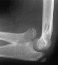

RADIOGRAPHS:

These demonstrate the left elbow to have a bony synostosis of the proximal

radius and ulna, distal to the proximal radial physis but with anterior

dislocation of the radial head. There is no evidence of a bony synostosis

or dislocation in the right elbow. Internal Rotation